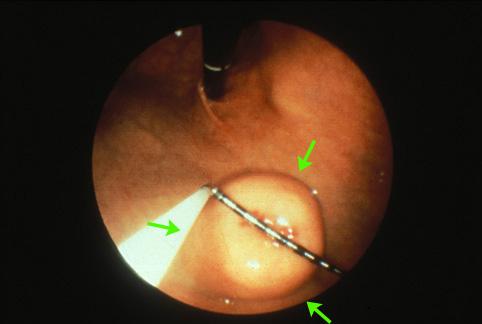

질환(병리주체)의 분류 양성 비상피성종양/신경계종양

부위(장기별) 위(부위)/체부

검사방법 내시경

종양의 육안분류 1형(종괴형)/

종양의 최대경(밀리미터) 35~40